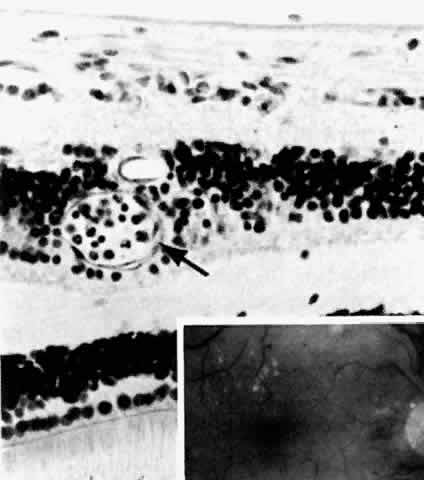

The earliest manifestation of diabetic retinopathy is the appearance of microaneurysms (Fig. 5, Color Fig. D). They appear as small red dots clinically and often are seen more readily on fluorescein angiography, where they fill and leak, with staining of the vessel wall.35 Histologically they are small “outpouchings” of the capillary vessel wall and are usually saccular but occasionally fusiform in shape. They can occur anywhere along the capillary network between the arteriole and venule.18 Some microaneurysms, however, do not fill with fluorescein and have been shown to be thin-walled capillary outpouchings filled with erythrocytes. They may represent either one stage of microaneurysm formation or a specific type of it.36

Fig. 5. Retinal capillary microaneurysm (arrow) is characterized by its thin wall and location in the capillary area of the retina (middle retinal layers) rather than the major vessel area (inner retinal layers). Inset. Fundus appearance of microaneurysms and hard or waxy exudates. (Main figure, H&E, × 176)

Fig. 7. Retinal capillary microaneurysm (RCM). A. RCMs occur in random distribution between the arteriole (a) and venule (v). “Young” RCMs are seen as saccular capillary outpouchings with proliferated endothelial cells (arrows). “Old” RCMs appear as solid black balls with their lumens obliterated by PAS-positive material. Note the darker color of the capillaries with thickened basement membranes and arteriolar-venular connections. B. Very large RCM (arrow) or the tiny hemorrhages associated with abnormal vessels are probably responsible for the RCMs seen clinically. (A, PAS, × 40; B, PAS, × 115)